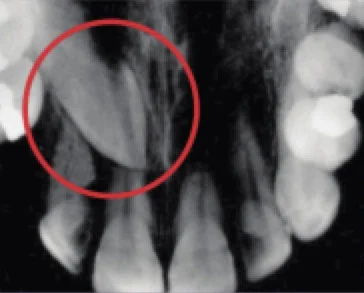

This occlusal x-ray shows a tooth that hasnot yet reached the surface (unerupted).